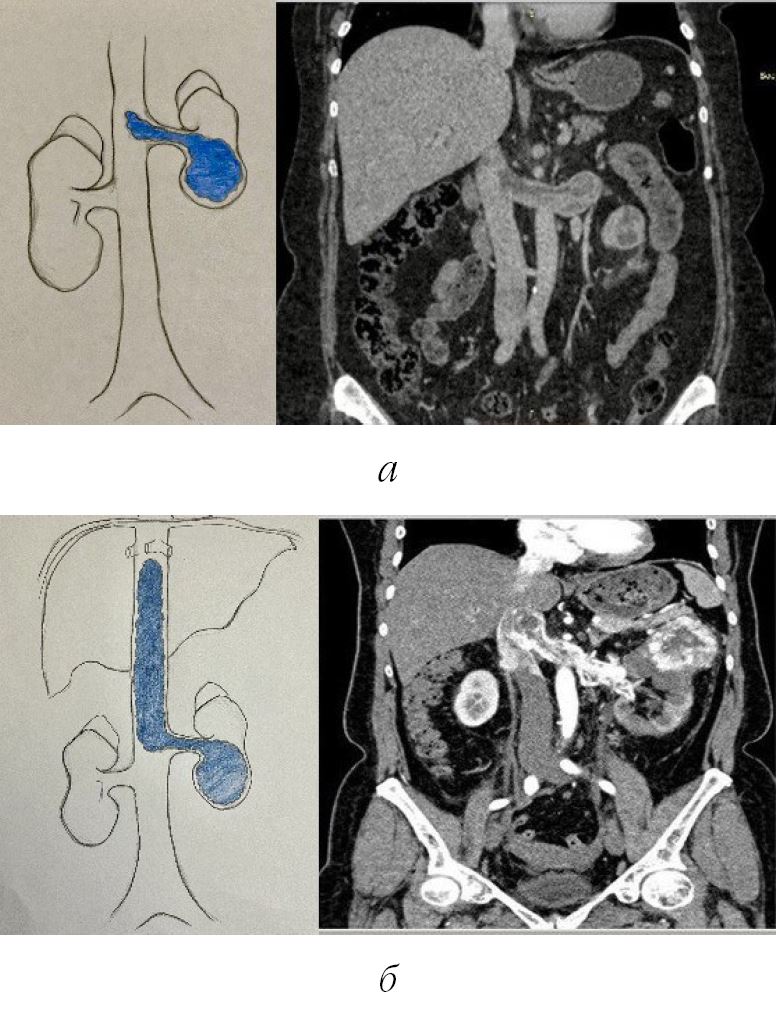

Опухолевый венозный тромб наблюдался у 100 % пациентов. В почечной вене он определялся у 54 человек; распространение в нижнюю полую вену не более 2 см – у 28 (1-й уровень тромба по Mayo) и более 2 см до устья печеночных вен у 18 (2-й уровень тромба по Mayo) (рис. 2).

Рис. 3. Визуализация перед операцией: опухолевый тромб расположен в левой почечной вене до нижней полой вены: а – 2 см – тромб соответствует 1-му уровню по Мейо; б – тромб соответствует 2-му уровню по Мейо